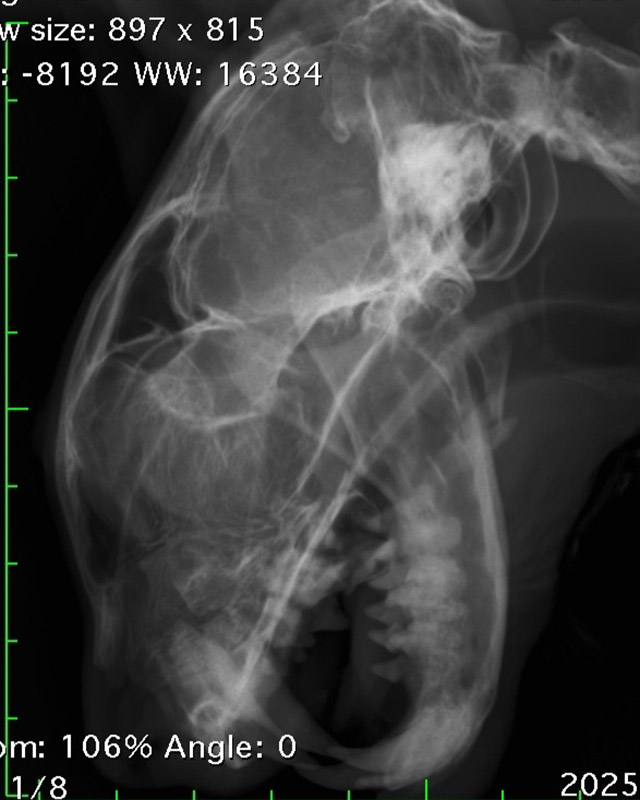

下顎骨骨折

雑種猫(14歳)

犬に咬まれた

手術前

手術後